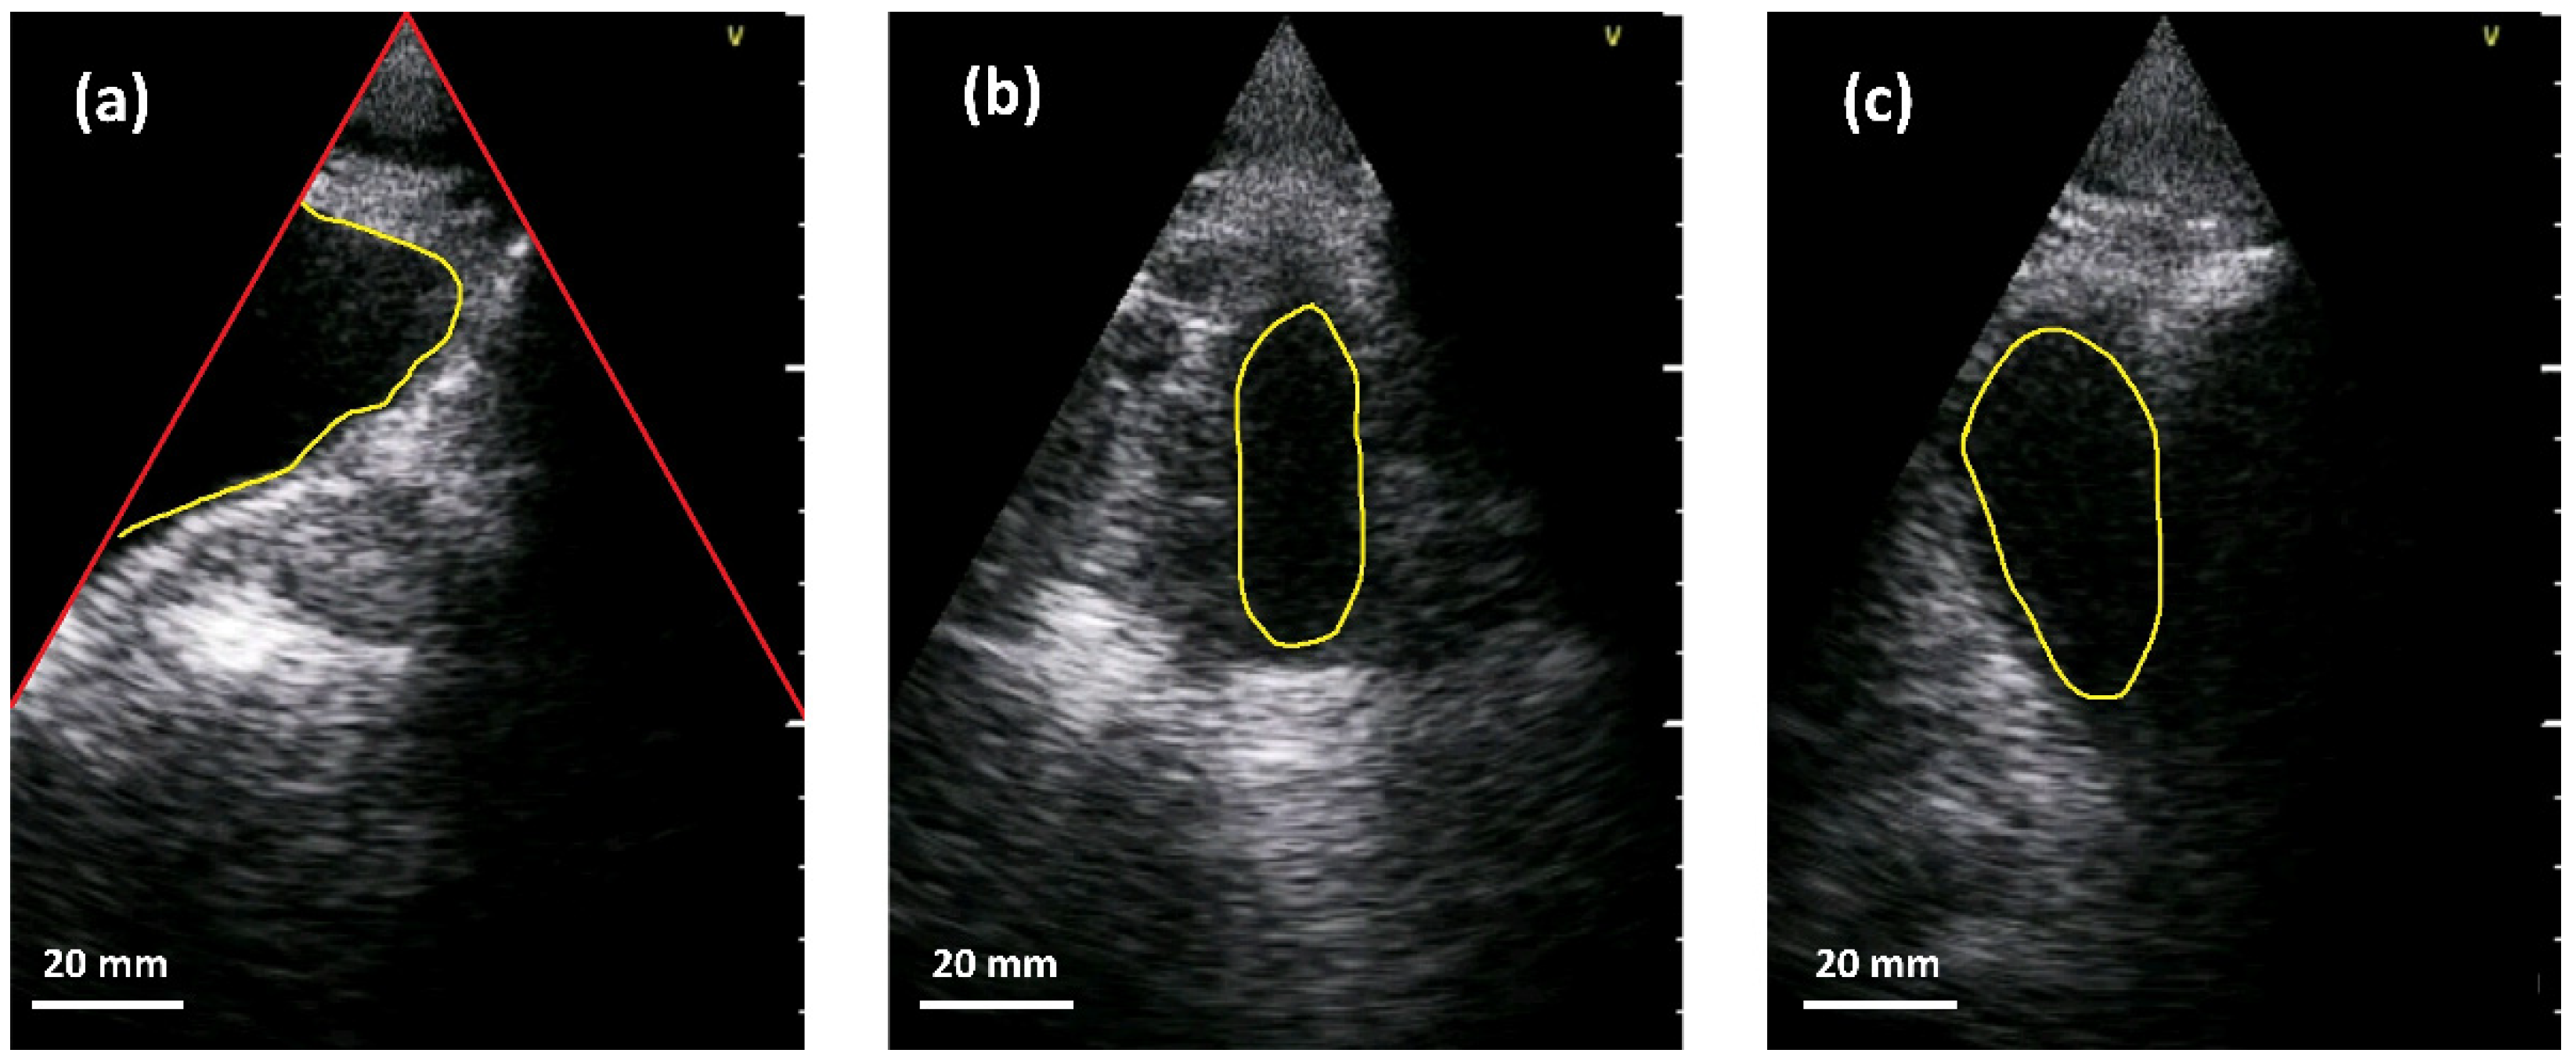

We trained a neural network to segment the bladder into abdominal ultrasound images and encountered two main challenges when implementing the network. On the one hand, the limited space and computational resources available at inference time and on the other hand, the quality of abdominal ultrasound images can be very challenging. Figure 4 shows an example: in the left sub-figure, a (partially filled) bladder appears mainly as a dark region in the image since little sound is reflected by the fluid. In addition, the bladder is only partially imaged and merges seamlessly into the black area outside the ultrasound fan. This situation is usually the case in corpulent patients. As can be seen in the upper part of the segment, weak echoes might occur in cases where the side lobes of the ultrasound beam intersect with the bladder tissue. A very different situation is shown in the middle sub-figure. Here, the (almost empty) bladder is located in the middle of the ultrasound fan. Lastly, the right sub-figure depicts a situation where other anatomical structures, e.g., the pubic bone or the colon, generate a large dark region that might fuse with the bladder. Please note that the appearance of different anatomical parts can be very similar in the images.

Figure 4.

Examples of bladder segmentation (yellow). Red lines in the left sub-image indicate the borders of the ultrasound fan above which there is no valid information. (a) Partially visible bladder. (b) Almost empty bladder near the center of the US-fan. (c) Additional dark regions due to pubic bone shadow or colon.